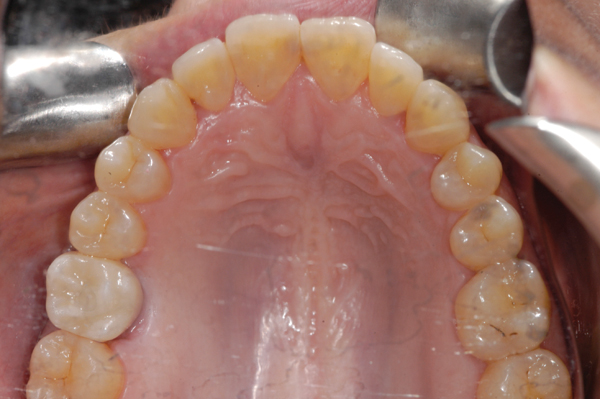

Finally, the amount of attached gingiva is evaluated. There is disagreement regarding the need for attached gingiva around implants,16,17 but the generally accepted minimum is 2 mm.18,19 A zone of 3 mm is recommended by this protocol for esthetics. A simple method of evaluation is to place a periodontal probe against the cementoenamel junctions of the adjacent teeth. At the midpoint between the adjacent teeth, the buccal aspect of the implant should exit 2 mm lingual to the probe. Therefore, if attached gingiva extends 1 mm facial to the probe, there should be adequate keratinized tissue. If the minimum requirements of bone volume and attached gingiva are not met, ridge augmentation and/or soft-tissue grafting are needed prior to implant placement. If the minimum requirements are met, digital impressions of both arches are obtained before dismissing the patient.

Figure 1. Digitally designed restoration for an edentulous space.

Figure 1